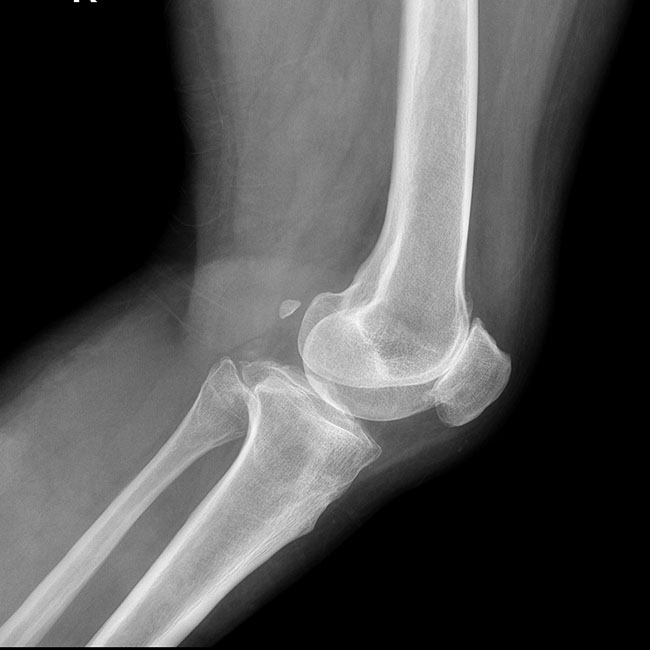

臨床樣本